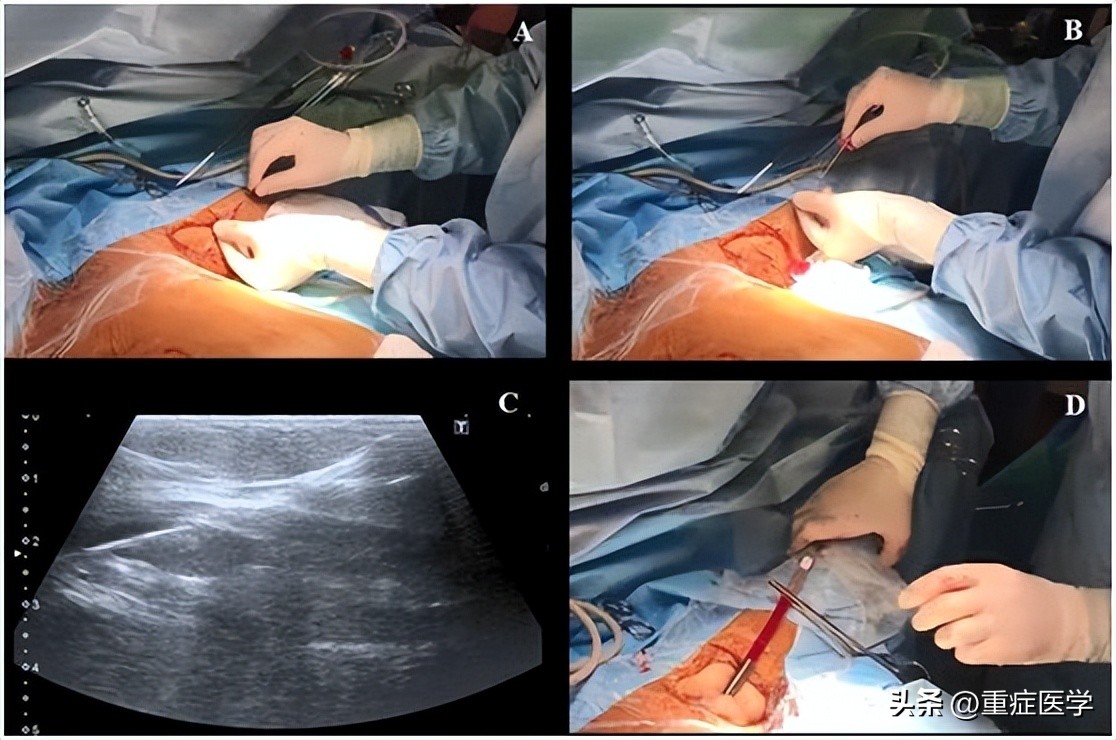

当在腋静脉腔内观察到针尖的斜面时(一个白点),可以很容易地确定穿刺针在血管内的位置(图2C)。也可以通过回抽血液1-2ml来确认穿刺针的位置是在静脉内。当患者血压较低时,无搏动性血流出现并不能排除穿刺到动脉的可能。随后置J形导丝,导丝的位置也可能在超声实时下确认(图3,A-C)。也可以通过颈部超声探查来排除导丝进行左侧颈内静脉。导丝置入长度应限定在20cm,以避免引起心律失常。随后扩张皮肤穿刺点,用Seldinger技术置入导管。在输注任何液体之前,回抽确认导管远端是否在血管腔内,随后再用肝素盐水冲洗导管。导管置入深度为20cm。

图3,A和B置入导丝,C超声视窗下可见静脉的导丝;D 把导管固定